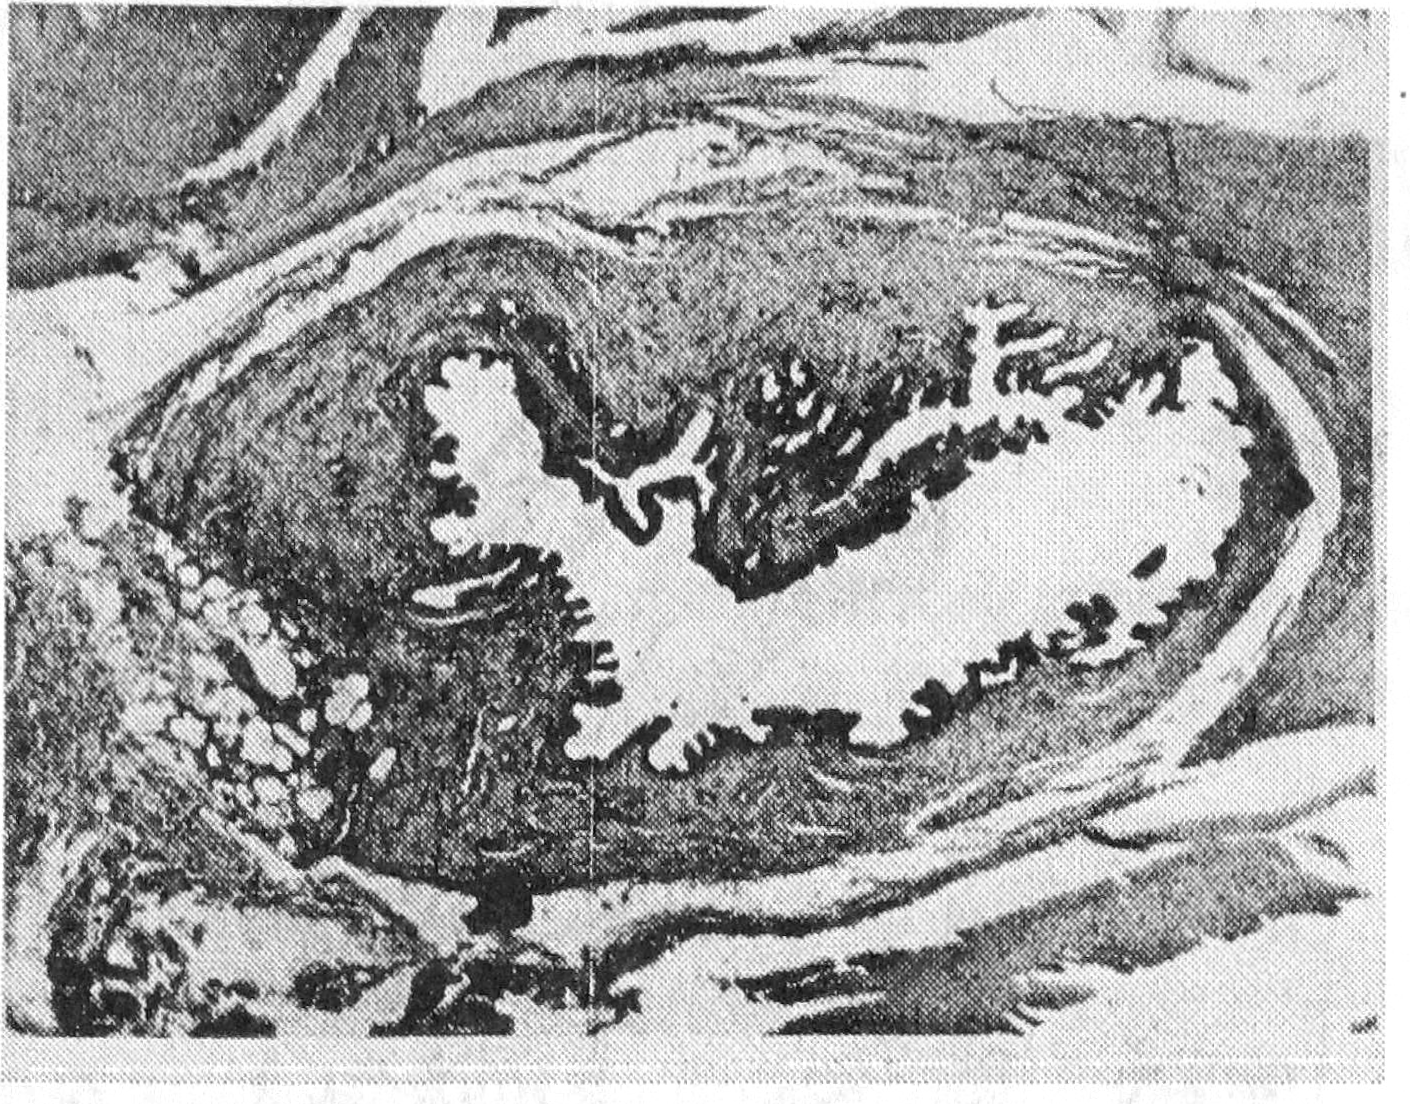

Через месяц после создания анастомоз выглядел следующим образом (рис. 4); толстая собственная пластинка холедоха переходила без отчетливых границ в подслизистую тощей кишки, причем продуктивные очаги были минимальными. Имели место небольшие периваскулярные очаги гистиоцитов и фибробластов по 3—6 клеток, сливавшиеся с гиперхромными клетками перителия венул и капилляров. Слизистая холедоха отличалась неравномерной невысокой складчатостью, эпителий был однослойным цилиндрическим. Пигмент в нем отсутствовал, бокаловидные клетки были редкими. Мышечные волокна холедоха без особенностей. В анастомозе какой-либо патологии, кроме очагового отека, не отмечалось.

Рис. 4. Микропрепарат анастомоза через один месяц, х 200.